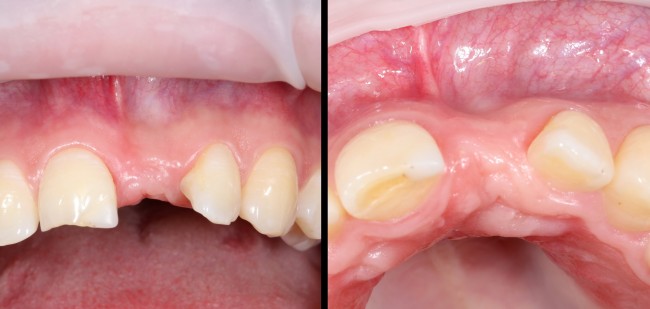

Через год после травмы, девушка обратилась в нашу клинику для восстановления отсутствующего зуба. К тому моменту у нее уже был временный съемный протез, изготовленный в вышеозначенном стоматологическом кабинете, ну и, вот какая клиническая картина:

Хочу спросить вас, уважаемые друзья, можно ли в таком состоянии и при таких объемах альвеолярного гребня поставить имплантат в область отсутствующего зуба? Безусловно, можно. Для этого нужно просто взять имплантат потоньше и поставить его подальше, в сторону неба — и он нормально интегрируется.

Возможно ли получить на подобном импланте более-менее приемлемый эстетический и функциональный результат? Вряд ли. Если за пределами эстетически значимой зоны мы можем пойти на эстетические компромиссы (все равно никто не увидит), то проблемы с эстетикой в области передней группы зубов… да еще у девушки…. так можно человеку всю личную жизнь испортить.

Через 3 месяца мы готовы приступить к формированию десны. И каким-то невероятным образом, у нас получился даже избыток слизистой оболочки. Что, безусловно, очень даже хорошо:

По фотографии хорошо видно, как изменилась форма альвеолярного гребня после операции.

Через несколько месяцев после формирования десны, ортопед изготовил постоянную коронку:

И, на мой взгляд, получилось это очень неплохо. Сравните с тем, что было «до-«:

Наша пациентка это знает, поэтому через год заглянула к нам в клинику. И вот, что мы увидели:

На мой взгляд, это — уже хоть какой-то результат лечения. И, по мнению пациентки, с поставленной задачей мы справились.